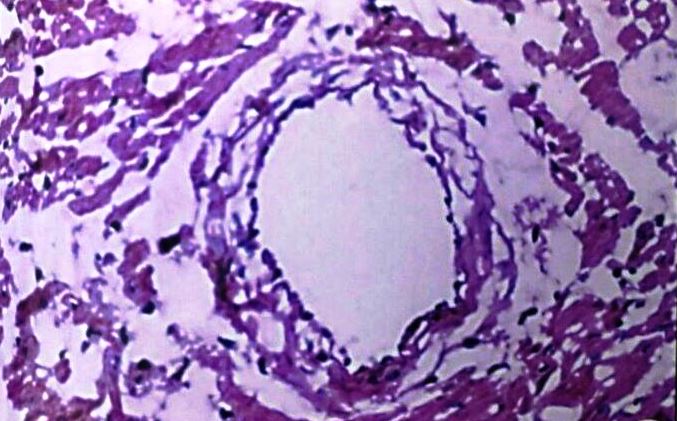

Coronary artery

The coronary artery of control group animals showed the lumen encircled by the arterial wall, which consisted of three distinct layers tunica intima, tunica media and tunica adventitia. The coronary arteries of hyper-cholesterolemic rabbits (Group II) showed foamy appearance, due to the presence of a large number of lipid-filled macrophages. The wall becomes very thick, reducing the size of the lumen. Our findings demonstrated that concurrent administration of C. verum extract with high cholesterol diet caused a significant increase in lumen size and thickening of tunica intima due to foam cell showed a reduction. However, the plaque has restricted to grow in concurrent groups, but coronary artery of low dose level treated group showed some fatty changes. (fig. 7-10)

Fig. 7: Coronary artery of control rabbit

Fig. 8: Coronary artery of rabbit after Athero Diet feeding for 120 d

Fig. 9: Coronary artery of rabbit–Athero Diet+C. verum 200 mg concurrent (120 d)

Fig. 10: Coronary artery of rabbit-Athero Diet+C. verum 300 mg concurrent (120 d)